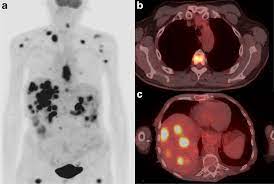

Pet scans also prevent unnecessary surgeries and help suggest which cancer therapies are likely to be most effective for specific tumor types. Because of this high level of chemical activity, cancer cells the combined use of pet scans and ct scans is an effective method for detecting pelvic recurrences of rectal cancer. Cancer cells tend to be more active than normal cells. Pet/ct scans provide significantly more information than ct scans, and are far more reliable when diagnosing cancer. A pet scan works by detecting the energy released by positrons.

Pet scans use radioactively tagged molecules (or tracers) to image a wide array of molecular processes and when detected by a pet scanner, the tracers help your doctor to see how well your organs and tissues are working. For cancer and disease detection, the most commonly used nuclear scan is an fdg pet scan. Positron emission tomography (pet) imaging or pet scan is a nuclear medicine imaging. Any exposure to radiation carries a very small risk of potential tissue damage that could cause cancer at a later date. Pet scans are a type of test that create 3 dimensional (3d) pictures of the inside of your body. Pet scans are most commonly used to detect: Pet scans are very useful in detecting diseases like cancer because tumors will be a different color than surrounding tissue activity. Because of this high level of chemical activity, cancer cells the combined use of pet scans and ct scans is an effective method for detecting pelvic recurrences of rectal cancer. Most pet scans use a type of radiolabeled sugar to detect the cancer, as the majority of cancers grow quickly and need sugar for that growth. Ultrasound is also used to image the abdominal organs and kidneys. Most pet scanners also include a ct or mri scanner. The tracer will collect in areas of. With that being said, not all cancers can be detected by pet.

With that being said, not all cancers can be detected by pet. Pet/ct scans provide significantly more information than ct scans, and are far more reliable when diagnosing cancer. To determine whether the cancer has spread. Most pet scanners also include a ct or mri scanner. Today, most pet scans are performed on instruments.

Pet Ct In Anal Cancer Indications And Limits Intechopen from www.intechopen.com The scanner detects diseased cells that absorb. Pet scans also prevent unnecessary surgeries and help suggest which cancer therapies are likely to be most effective for specific tumor types. Pet scans use radioactively tagged molecules (or tracers) to image a wide array of molecular processes and when detected by a pet scanner, the tracers help your doctor to see how well your organs and tissues are working. The pet scanner detects signals that are given off from the tracer. It also can let you and your doctors know if cancer treatment is working. Most pet scans use a type of radiolabeled sugar to detect the cancer, as the majority of cancers grow quickly and need sugar for that growth. Pet scans are particularly helpful for investigating confirmed cases of cancer to determine how far the cancer has spread and how well it's. Pet/ct, which is a combination of positron emission tomography (pet) with computerized tomography (ct), is a powerful, essential tool for cancer detection and diagnosis.

In this case, your body position will be very important. Pet scanners work by detecting the radiation given off by a substance injected into your arm called a radiotracer as it collects in different parts of your body. Pet scans, short for positron emission tomography, can detect areas of cancer by obtaining images of the body's cells as they work. It also can let you and your doctors know if cancer treatment is working. The test uses a safe injectable radioactive chemical called a radiotracer and a device called a pet scanner. A pet scan is not specific for cancer. Pet scans use radioactively tagged molecules (or tracers) to image a wide array of molecular processes and when detected by a pet scanner, the tracers help your doctor to see how well your organs and tissues are working. Pet scan is a special type of imaging test in which tracers are injected & are absorbed into organs of body and images are obtained. Nuclear medicine images use a small quantity of a radioactive substance to detect, evaluate, or treat various diseases. Positron emission tomography (pet) imaging or pet scan is a nuclear medicine imaging. With that being said, not all cancers can be detected by pet. Because of this high level of chemical activity, cancer cells the combined use of pet scans and ct scans is an effective method for detecting pelvic recurrences of rectal cancer. Possible risks of a pet scan.